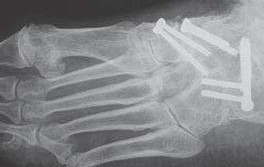

Es kommen verschiedene technische Möglichkeiten der operativen Versorgung in Frage.  Verwendung finden vor allem winkelstabile Plattensysteme, Schraubenosteosynthesen, Klammern, intraossäre Nagelsysteme, temporäre Kirschnerdraht-Transfixationen, Einbolzen von trikortikalem Span und Anlagerung von Spongiosa aus dem Beckenkamm oder dem Tibiakopf  (Abb. 2 und 3).

Durch die Arthrodese soll, wie oben beschrieben, eine Schmerzreduktion, eine Wiederherstellung der Fußstabilität und eine Korrektur der Fußstellung erreicht werden. Hierbei gibt es unterschiedliche Ansätze. Einige Autoren versteifen stets die mediale und laterale Säule bei TMT-Arthrosen 22. Andere Autoren sind der Meinung, dass nur die mediale Säule versteift werden sollte 18. Andere wiederum dehnen den Eingriff aus und beziehen die Cuneiforme-Gelenke mit in die Lisfranc-Arthrodese ein 21. Grundsätzlich zeigt sich der Trend, dass nur isoliert die arthrotischen und symptomatischen Gelenke versteift werden, ferner die Zugangswege klein und die Resektionsflächen der einzelnen Gelenke nur bis zur subchondralen Spongiosa eröffnet werden 23.